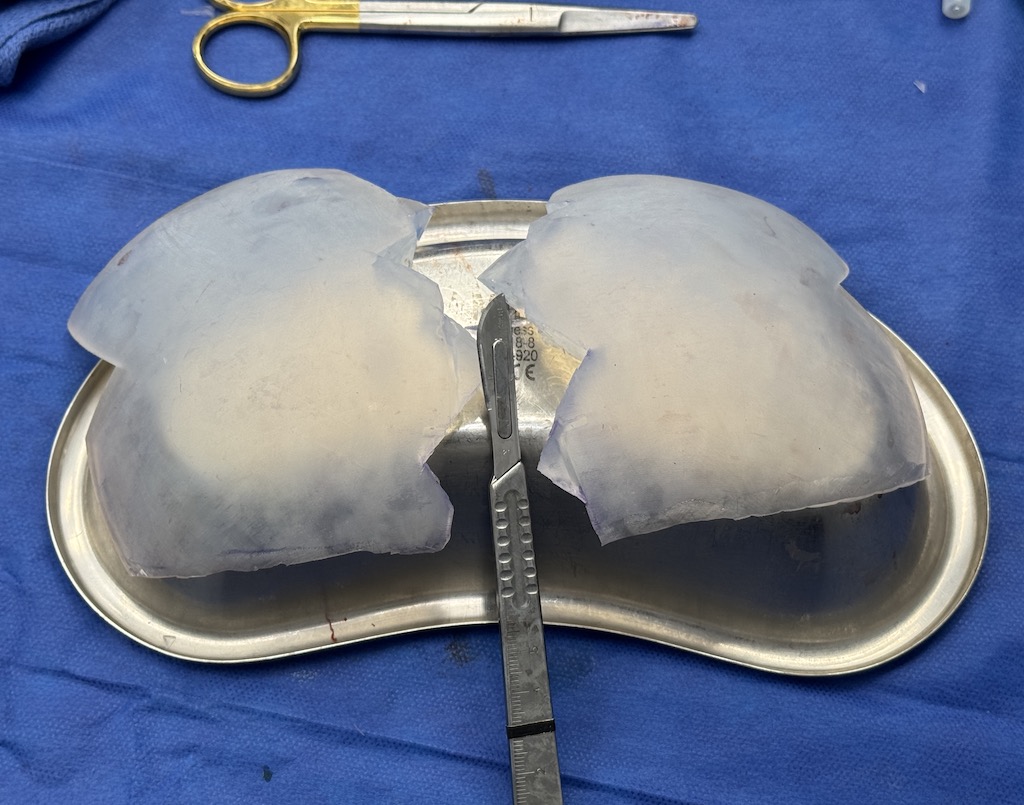

Desire for major head reshaping with a taler and wider head shape.

Placement of large two piece custom skull implant through a sagittal scalp incision.

Desire for major head reshaping with a taler and wider head shape.

Placement of large two piece custom skull implant through a sagittal scalp incision.